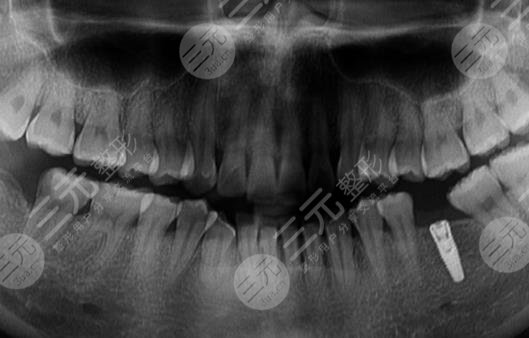

到醫(yī)院進行面診的時候,醫(yī)生先讓我咬了牙齒的模型,然后又拍了牙片,選擇了牙齒的種植體,一星期之后,我來到了醫(yī)院進行種植牙。整個種植牙的過程是很快的,而且因為打了局部mz也沒有任何的感覺。大家現(xiàn)在可以看到我的種植牙是十分成功的,而且看上去十分的潔白,跟周圍的牙齒形成了鮮明的對比。